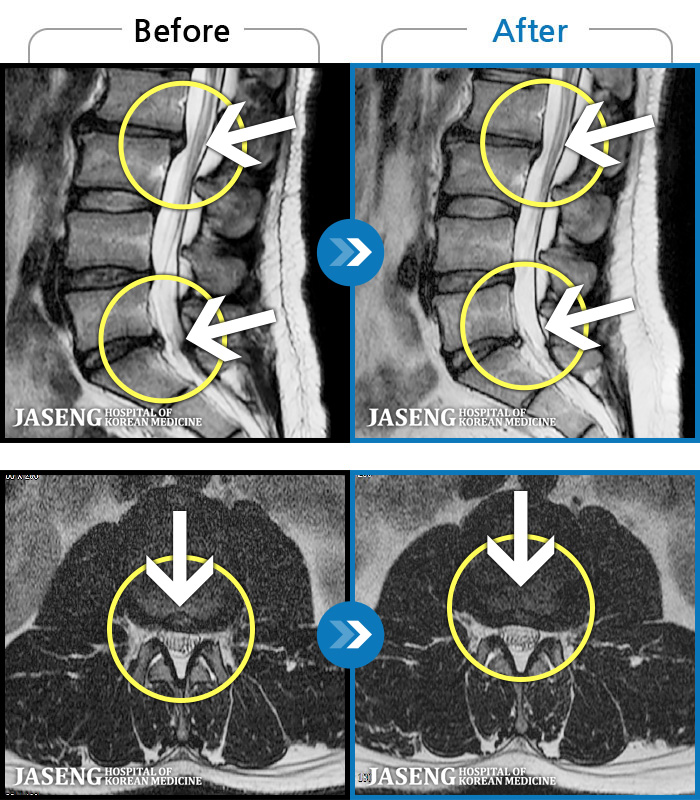

ȯںп Ǹ ǿ ԿǾ, ο ġ ۿ Ƿ ġḦ Ͻñ ٶϴ.